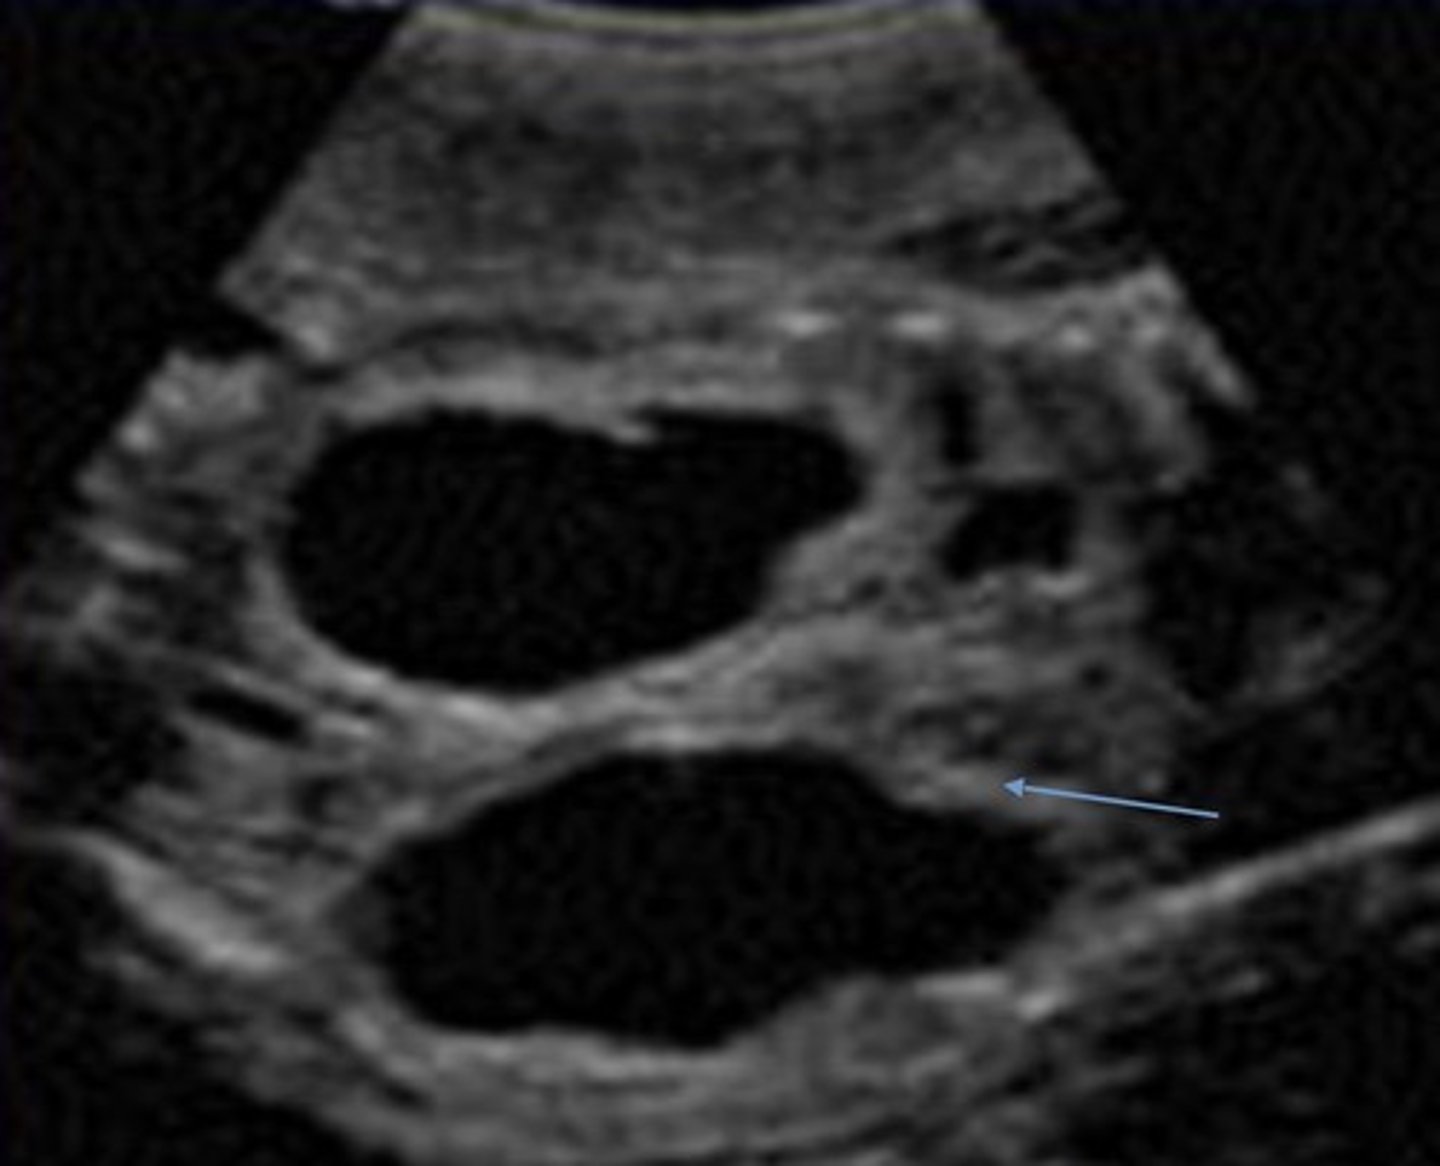

Posterior Urethral Valve Obstruction

Only in boys

Causes bilateral hydronephrosis

Thick bladder walls

Keyhole bladder appearance